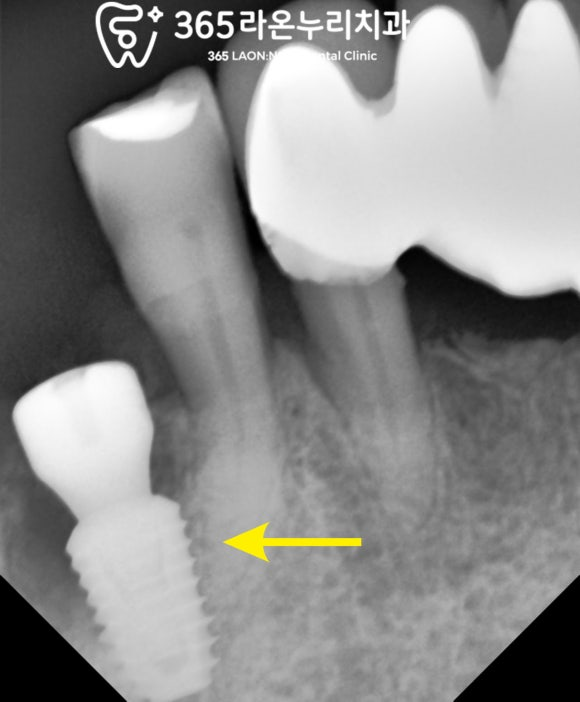

자세히 보기 위해

치근단 x-ray 사진을 촬영했습니다.

예상대로 뿌리 주변 뼈가

모두 녹아서 흔들림이 있기에

하루빨리 발치를 하여

뼈가 더 녹는 것을 막아줘야 됩니다.

겉으로 봤을 때도 염증이 보이고

통증도 동반된 채로 불편하다고 하셔서

신속한 조치가 필요해 보이네요.